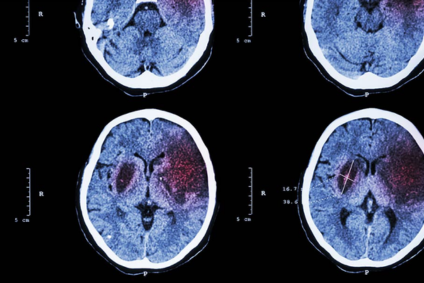

ictus y linfoma diferencia

Escribano, A. (2017). Existen dos tipos de ictus, el isquémico y el hemorrágico. [Fotografía]. Recuperado de www.tusdudasdesalud.com

En primera instancia, sabemos que el linfoma cerebral primario se desarrolla lentamente. Así, las personas que lo presentan suelen notar síntomas como cefaleas persistentes, cambios cognitivos o debilidad progresiva que se agravan en semanas o meses. Por ende, el avance gradual permite que los síntomas evolucionen antes de que se confirme el diagnóstico.

Por el contrario, el ictus aparece de forma abrupta. En cuestión de minutos, una persona puede experimentar parálisis en un lado del cuerpo, dificultades para hablar o pérdida de visión. Dicho inicio súbito refleja su naturaleza vascular, es decir, una obstrucción repentina del flujo sanguíneo en el ictus isquémico o la ruptura de un vaso en el ictus hemorrágico (Schaff y Grommes, 2022).

En contraste, el ictus se confirma con tomografía computarizada o resonancia magnética, que identifican hipoperfusión o hemorragia según el tipo. A su vez, el ictus isquémico requiere trombólisis o trombectomía, mientras que el hemorrágico demanda cirugía para controlar la hemorragia y reducir la presión intracraneal (Kuriakose y Xiao, 2020).